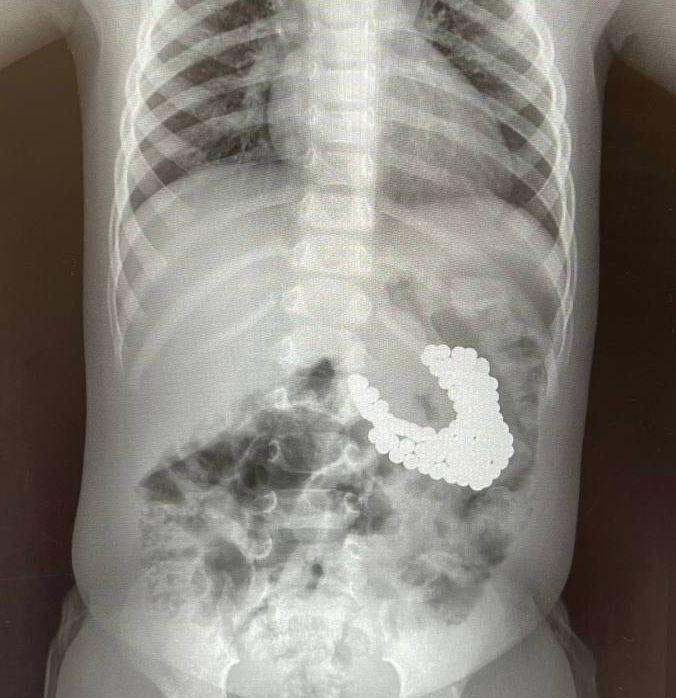

Сосиска, гелиевый шар и нож — эти и другие предметы в пациентах находили московские врачи в 2026-м.

Фото - @moscowach